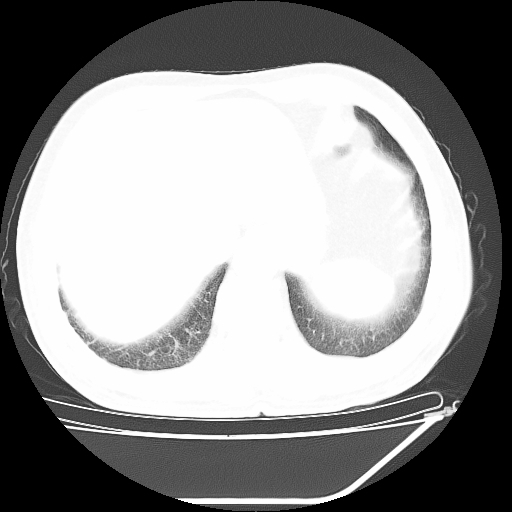

胸片 结节影

胸片 结节影,

看片诊病之典型急诊胸片分享

肺结节影(疾病)

胸部平片右下肺结节影(错构瘤,钙化不明显